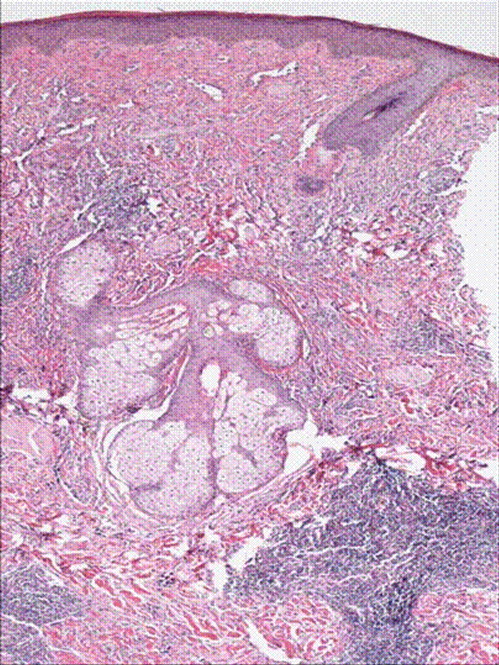

A 50 year old male with past medical history of diabetes, hypertension was diagnosed with angiosarcoma localized to the face (Figure 1 & Figure 2). The patient had baseline mild coagulopathy before start of chemotherapy most likely from the angiosarcoma. He received the first cycle of paclitaxel and bevacizumab but required hospitalization four days later for chest pain and acute coronary syndrome was ruled out. He then developed febrile neutropenia with an ANC of 0.0 and progressive pancytopenia. On day 9 of chemotherapy, the patient had a platelet count of 12 K/μ L with hemoglobin of 6.1gm/dl, hematocrit of 18% and WBC count of 3 k/μ l. The peripheral smear revealed many schistocytes, in addition elevated LDH 1112U/L, with an indirect bilirubin of 2.62 mg/dl, total bilirubin of 3.80mg/dl, and a haptoglobin of less than 10. His coagulopathy progressed with a PT of 17.3, PTT 65.3, fibrinogen degradation products (FDP) which were less than 10 on day 6 post chemo, were more than 40 on day 8 and his D-Dimers were 13.5 mg/l(Figure 5). ADAMTS13 level was drawn and though his creatinine and mental status remained normal, plasmapharesis was initiated with the presumptive diagnosis of thrombotic thrombocytopenic purpura (TTP).

H& E stain of punch biopsy of the lesion from the cheek showing infilterating vascular tumor.